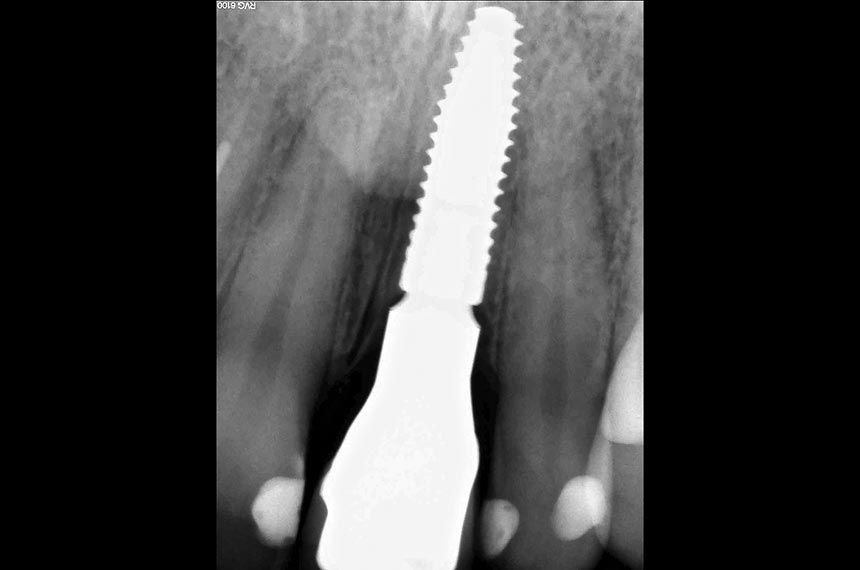

Following administration of local anesthesia, atraumatic tooth extraction was accomplished without flap reflection to preserve the interproximal papillae and the remaining buccal and lingual plates of bone. The extraction socket was carefully examined for dehiscences and fenestrations and debrided of residual periodontal fibers using curettes. Following socket debridement, a Straumann Bone Level Tapered Implant (Regular CrossFit™ Connection Ø 4.1mm, SLA® 14mm) was placed in tooth position 21 (FDI) (Fig. 4). A surgical guide was used to help ensure ideal three-dimensional placement (Fig. 5). The implant showed adequate initial stability when placed with a torque driver at 35 Ncm. A customized provisional titanium cylinder (Temporary Abutment) was then placed and hand-tightened onto the implant and trimmed using a positioned guide to ensure the correct height (Fig. 6). The hollowed crown of the extracted tooth was relined with acrylic resin and adapted to the custom provisional abutment using a positioned guide to ensure exact positioning (Figs. 7, 8). The provisional shell was precisely finished with composite resin on the temporary abutment to recreate the cervical emergence of the extracted tooth (Fig. 9). A synthetic bone graft substitute (Straumann BoneCeramic) was placed between the buccal plate of bone and the implant in order to fill the space and maintain the soft tissue contour. After immediate implant placement and bone augmentation, a supraperiosteal envelope was made labial to the socket. These tunnels, used to accommodate the connective tissue graft, were dissected sharply with a microsurgical blade (Fig 10). Care was taken to leave the periosteum attached to the bone during dissection. A connective tissue graft from tuberosity was inserted into the prepared envelope space and secured with non-resorbable sutures (Fig. 11). The immediate provisional restoration was tightly screwed onto the implant by hand. The provisional restoration was adjusted to clear all contacts in centric occlusion and during eccentric movements. A periapical radiograph was obtained to ascertain the fit of the provisional restoration (Fig. 12).

Clinical situation at the end of the surgery (Fig. 13)